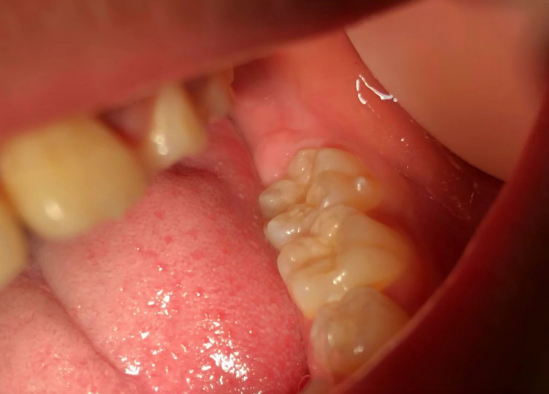

龋病是怎样形成的呢?

牙齿+含糖食物+细菌+时间→龋病

窝沟封闭仅对预防窝沟龋有效,

龋病还可能会发生在平滑的牙面

或者两颗牙齿的相邻面上。